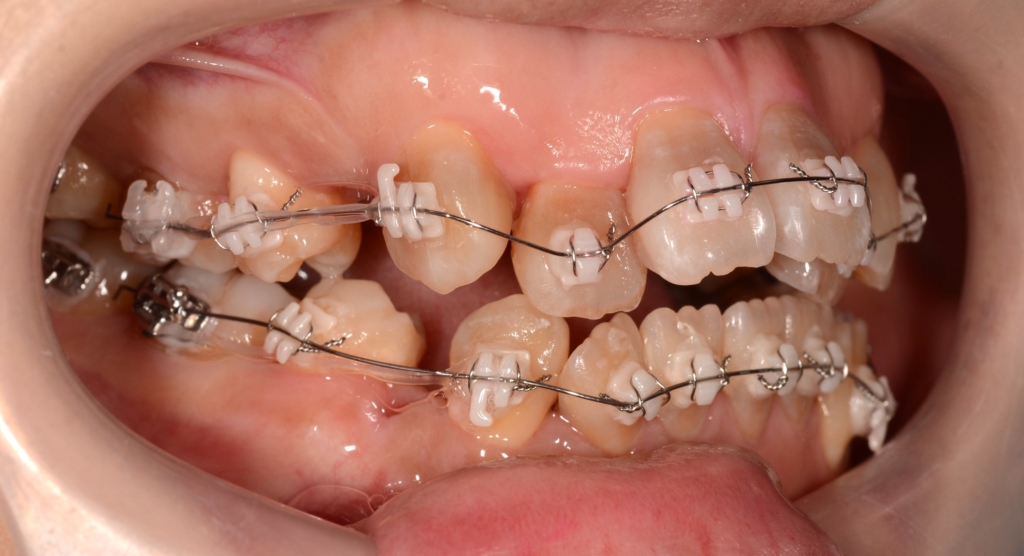

マルチブラケットシステム(スタンダード type)で矯正を開始。

先ず、上下とも前歯の凸凹の歯並び(叢生)の解消を図ります。

その後、前歯がきれいに並んだら、可及的に奥へ引っ込めながら残る隙間をなくしていきます。